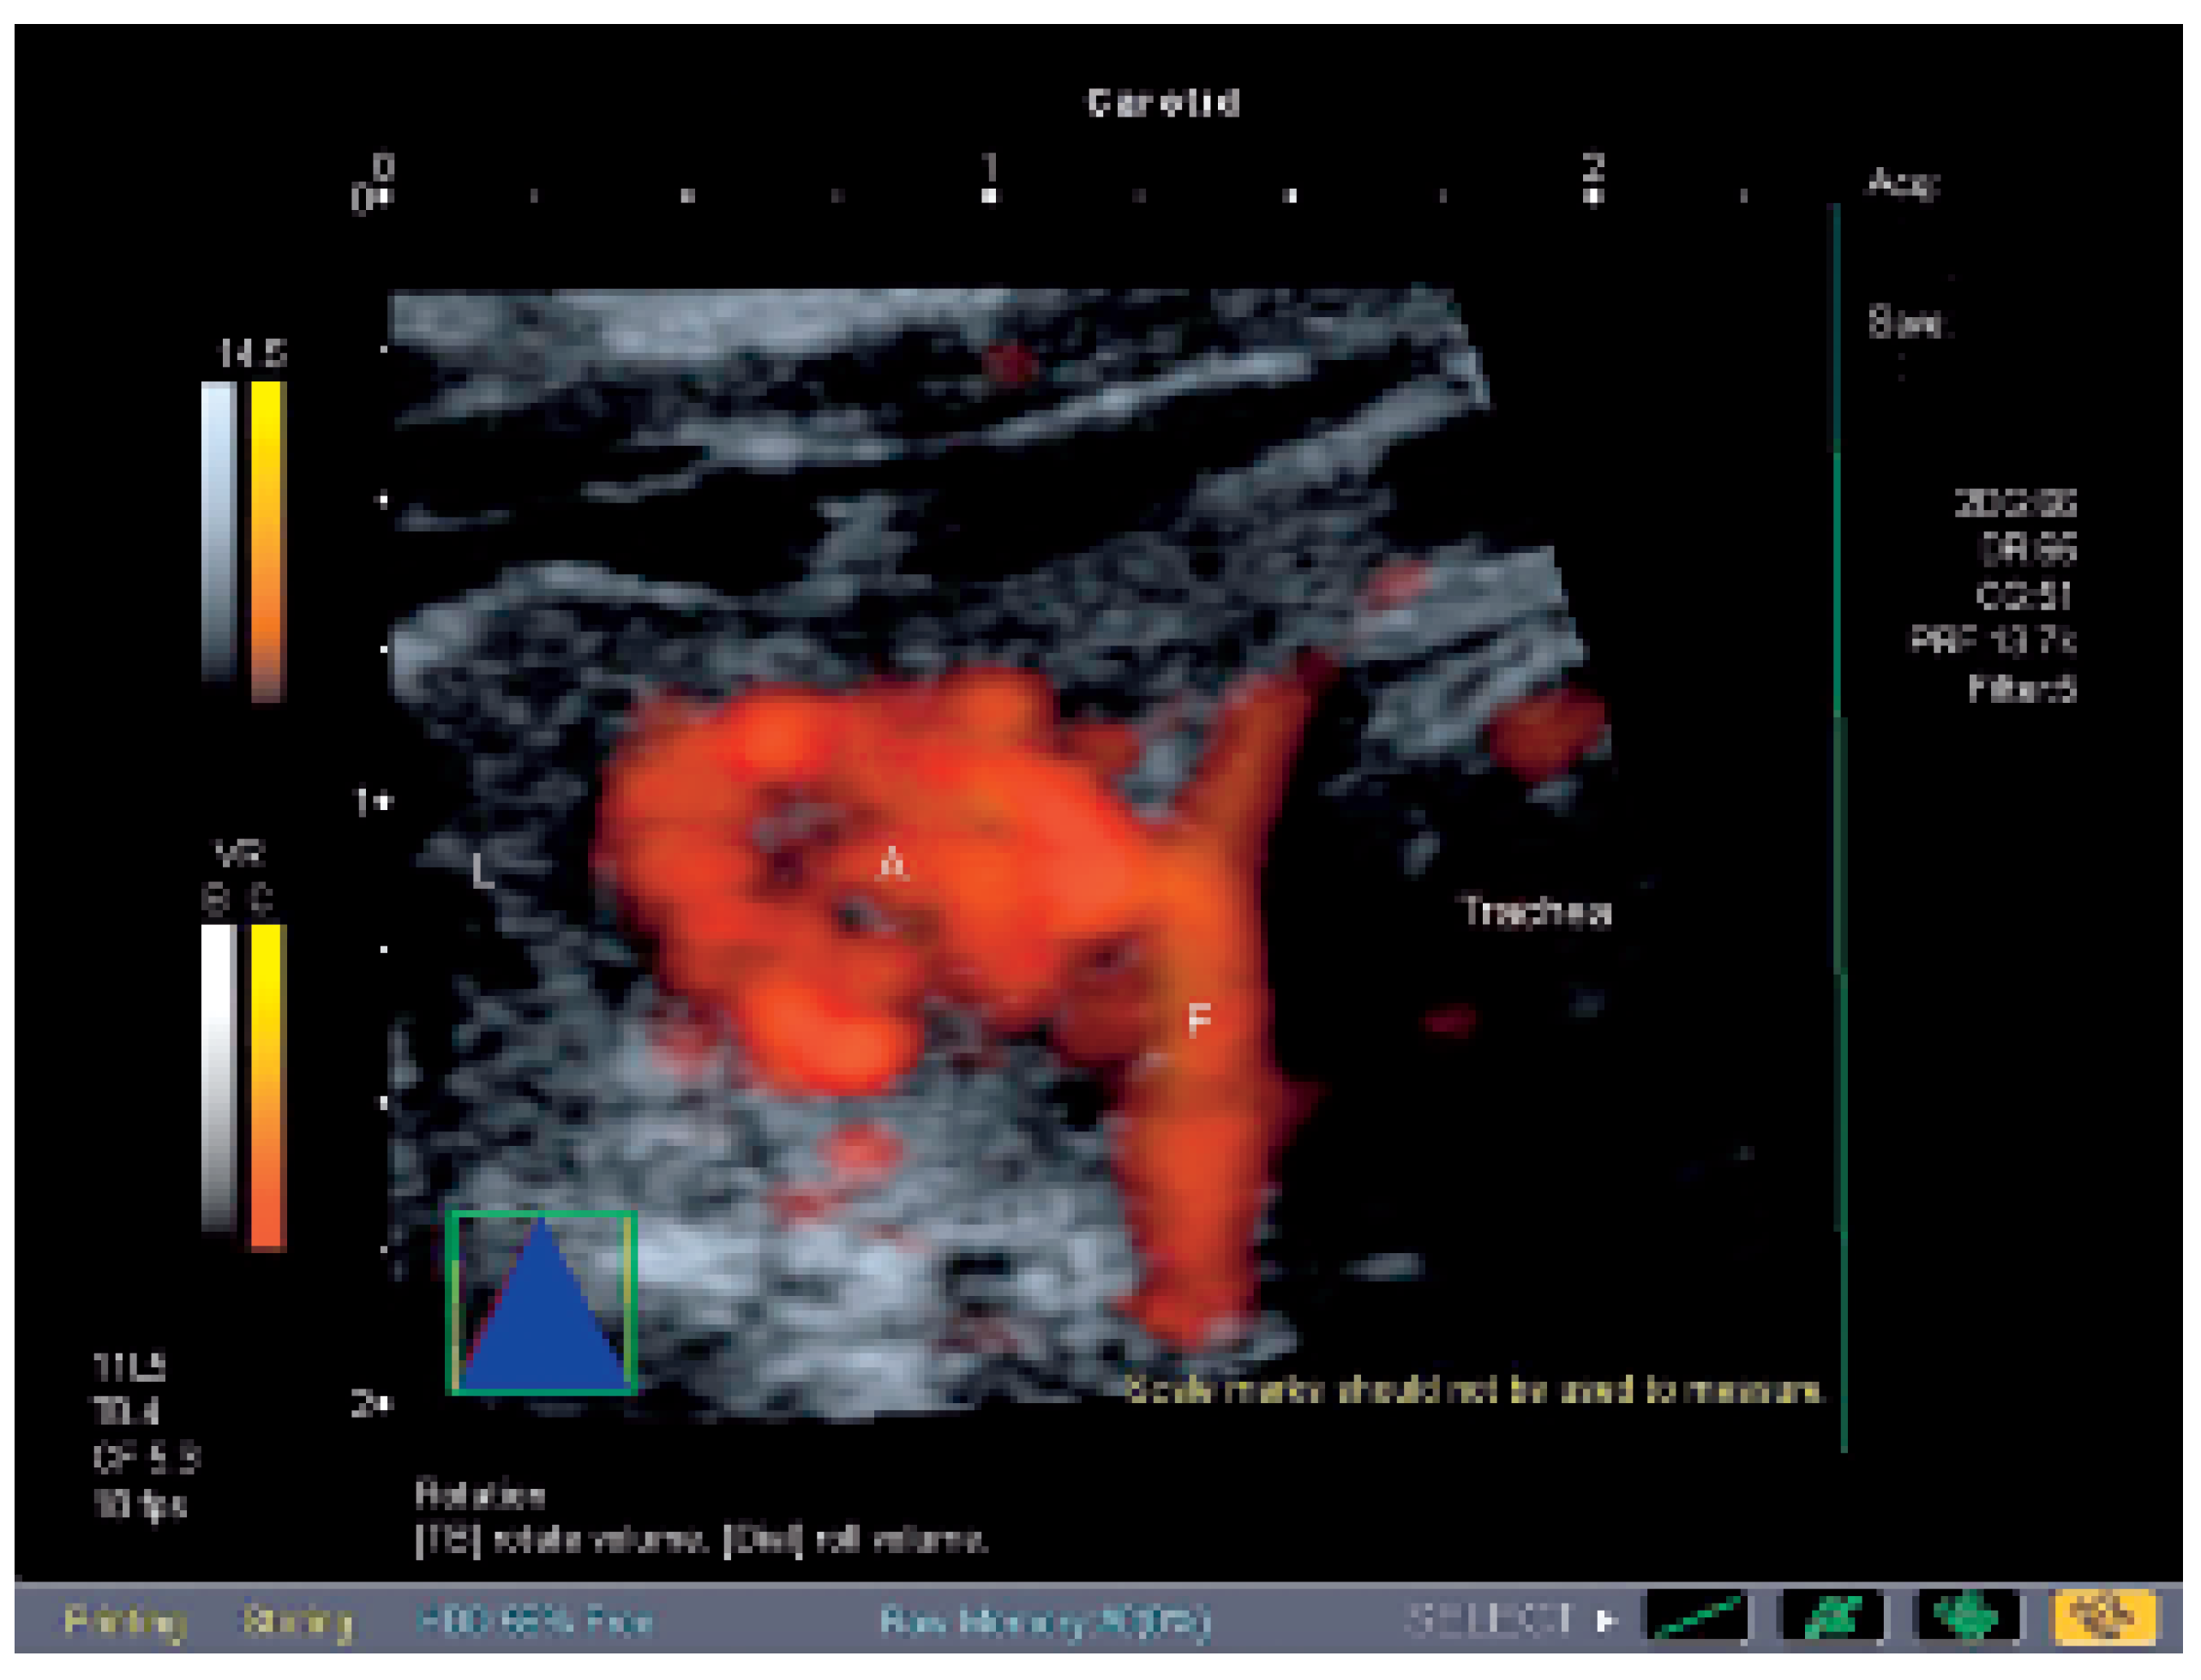

Autonomes Schilddrüsenadenom und Angiosonographie